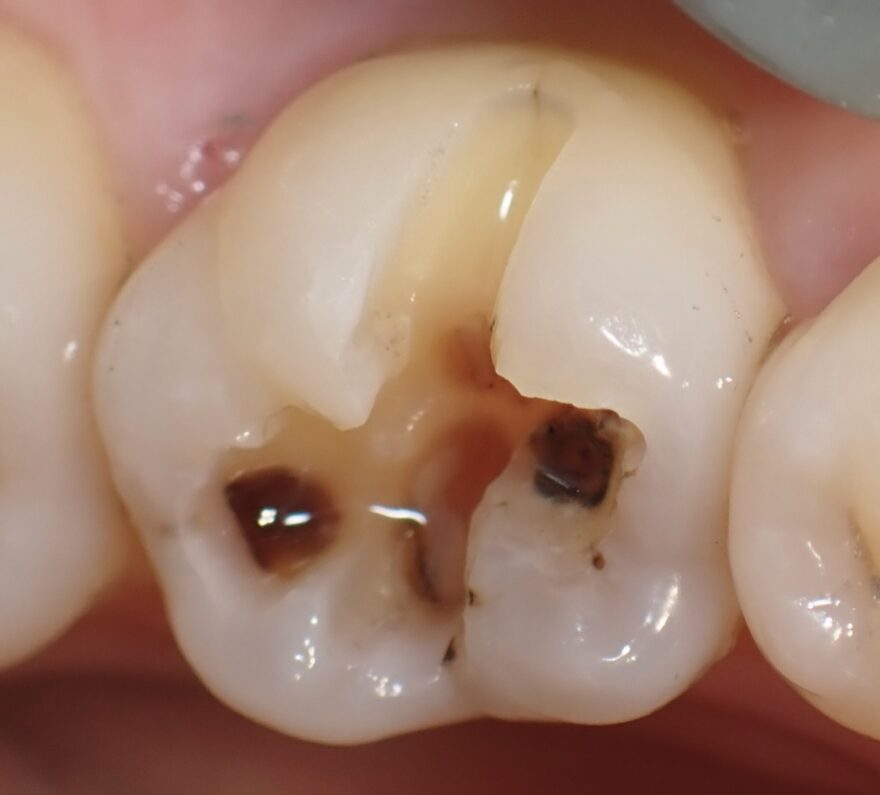

銀歯内部の虫歯をセラミックで修復した治療例

治療前後の経過写真

症状が全くなくても、銀歯を入れてから5年以上経過していると、深部でむし歯が再発していることがほとんどです。

銀歯は劣化が早く、隙間から細菌が侵入することが、むし歯再発の原因です。

茶色くても硬い箇所は温存しておいても問題ありません。

噛み合わせに関与している部分が失われてしまったため、セラミッククラウンを被せる必要があります。